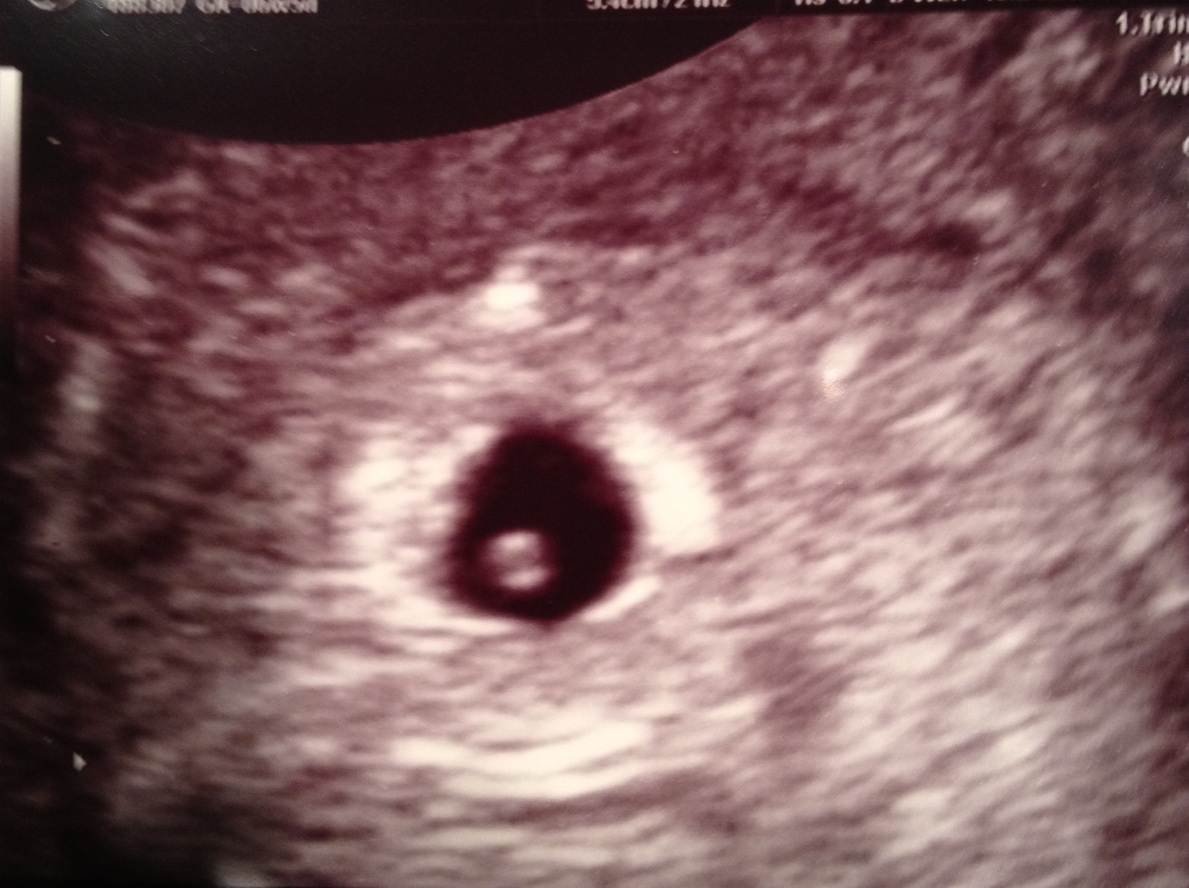

Ниже представлено фото плода на пятой неделе беременности, полученное с помощью УЗИ:

Как выглядит ваш маленький зародыш, который уже достиг размера апельсинового семени? На самом деле, он мало чем отличается от головастика, имея рудиментарную голову и хвост. Но не переживайте, в будущем вашему ребенку не суждено стать лягушкой.

| — Тревога или радость. | — Возможно, уже можно увидеть эмбрион и его сердцебиение. | — Сдайте необходимые анализы крови и мочи. |

Что происходит с вашим малышом на пятой неделе? Сердцебиение уже может быть заметным! В этот период вашему ребенку необходимо активно развиваться: формируются все основные и второстепенные системы организма, такие как пищеварительная, кровеносная, нервная и другие, а также органы, включая сердце, легкие и желудок. Первой системой, которая начинает функционировать, является кровеносная система, а сердце, которое вы сможете увидеть на раннем УЗИ, уже начинает биться. Обычно это становится заметным на 6 или 7 неделе, но иногда и на 5 неделе можно уловить этот момент.